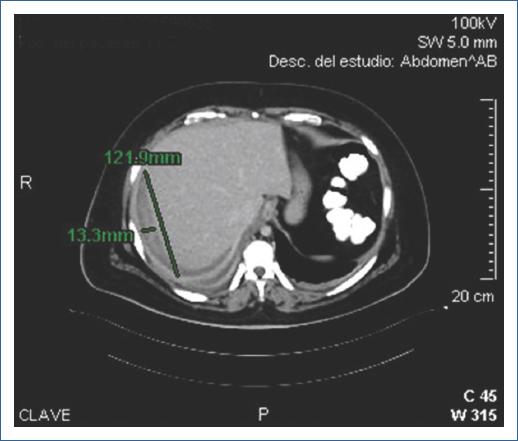

Paciente de sexo femenino de 46 años, con antecedente de hipertensión arterial sistémica en tratamiento. Ingresó para CPRE programada por diagnóstico de coledocolitiasis por ultrasonido. El procedimiento, realizado por el médico adscrito y asistido por el residente, tuvo un tiempo de canulación de 4 minutos, con tres intentos de canulación con guía hidrofílica. Se realizó esfinterotomía e identificación de defectos de llenado; se hicieron barridos con balón con salida de litos y colocación de endoprótesis biliar, con extracción exitosa. Posterior al procedimiento, la paciente presentó dolor en hipocondrio derecho. Laboratorios relevantes: hemoglobina (Hb) 10.1, BT 0.56, BD 0.08, BI 0.48; AST 106, ALT 20, FA 69, GGT 72, DHL 154, amilasa 78, lipasa 81. Se realizó TC que evidenció hematoma hepático subcapsular de 898 ml (Fig. 2). Se colocó catéter de drenaje percutáneo debido al volumen del hematoma, con gasto hemático adecuado durante su estancia hospitalaria y retiro del drenaje a los 7 días tras control ecográfico. Egresó tras 14 días de hospitalización con evolución favorable.